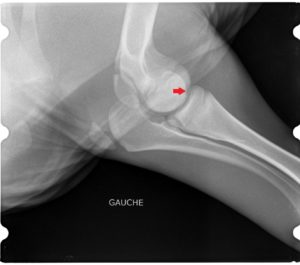

Le cas décrit ici est celui d’ une petite génisse Prim’Holstein de moins d’un mois. Elle avait une arthrite du coude, probablement faisant suite à une entérite (voir radiographies et échographie de l’articulation).